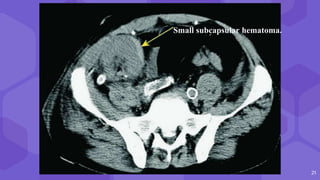

⬢ Large clinically significant hematomas- 4-8%

⬢ C/F Red blood cell count

Peritransplant Subcapsular

● Double contour

● Compression of renal collecting

system, vascular pedicle

21

Small subcapsular hematoma.